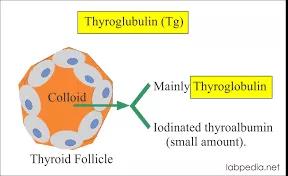

甲状腺是人体中非常重要的内分泌器官,外形像一只美丽的蝴蝶,通过分泌甲状腺激素促进物质和能量的代谢,对人体的多系统具有重要影响。近年来,随着人们体检意识的增强和超声诊疗技术的迅猛发展,甲状腺恶性结节的检出率呈逐年增高的趋势,而一旦确诊,颈部这只美丽的蝴蝶就面临着折翼的风险——外科手术切除。腺体切除、颈前瘢痕、终身服药像一幕幕阴霾,笼罩在患者的头上。 患者小Y是一个23岁年轻美丽的女孩儿,在哈医大一院超声医学科进行超声检查后,发现右侧叶有一枚大小约0.8cmx0.6cmx0.8cm的TI-RADS 4c类结节(图1),并且经过穿刺病理证实为甲状腺乳头状癌。这如同一个晴天霹雳般的坏消息,让这个女孩儿痛苦不已。如果选择手术切除,术后颈部的瘢痕、终身服药的不便、尚未结婚怀孕的现实难题,让小Y难以接受传统手术疗法。在了解到她的困扰后,哈医大一院超声医学科介入团队迅速启动科内会诊及病例讨论机制,在学科主任吴长君教授的提议下,决定采用超声引导下的射频消融治疗,对小Y的恶性结节进行局部灭活,并且尽可能保留正常腺体。通过术前审慎评估,细致准备,消融手术由超声医学科王俊峰副教授主刀。在实时超声的引导下,射频消融针精准的进入恶性病灶内,仅用时3分钟左右,消融范围就完全覆盖病灶(图2)。 治疗过程中,超声介入团队配合默契,采用多种技术保障患者安全,避免了甲状腺周围重要组织(血管、神经)的损伤。治疗取得了圆满成功。术后,小Y开心的笑了,超声介入团队也由衷的为她感到高兴(图3)。 哈医大一院超声医学科主任、博士生导师吴长君教授介绍,超声引导下射频消融治疗甲状腺乳头状癌,具有非常多的优点。在保障治疗效果的同时,可以满足患者个性化的需求。射频消融用时短,术后恢复快,无需终身服药,并且避免了颈部瘢痕,尤其对于爱美女性及拒绝终身服药的患者非常友好,是一种值得大力推广和应用的治疗技术。哈医大一院超声医学科介入团队秉承不断进取、精益求精的理念,着力打造甲状腺疾病诊疗一体化平台,为守护龙江人民的健康不懈努力!